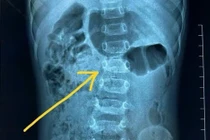

Bệnh viện Bãi Cháy đã phẫu thuật nội soi thành công khối u trung thất sát cột sống

cho bệnh nhân 38 tuổi, giúp bệnh nhân thoát khỏi nguy hiểm.